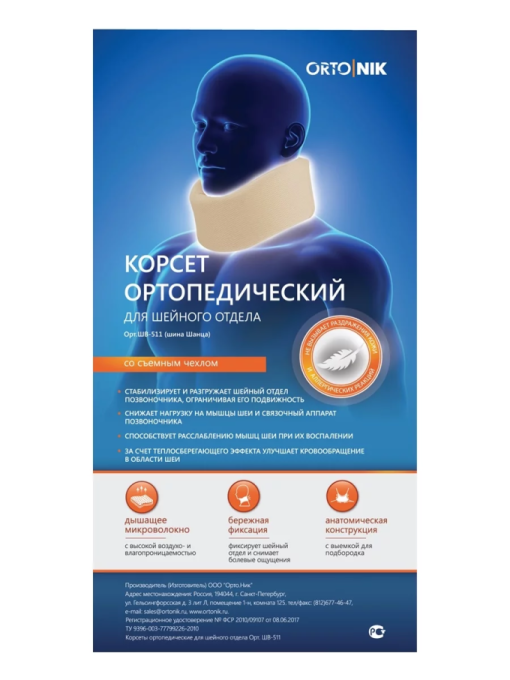

Арт: ШВ-511

Корсет ортопедический для шейного отдела, артикул Орт.ШВ-511